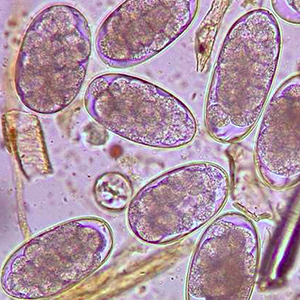

Les œufs de strongle présentent globalement la même morphologie ; ce sont des œufs ovalaires, à paroi lisse, possédant une morula et des faces latérales non parallèles. Leur taille est très variable (40 x 60 μm à 110 x 230 μm) et les groupes évoqués ci-dessus peuvent présenter des caractéristiques permettant d’orienter le diagnostic mais ces dernières sont à prendre avec précaution. Ces œufs, lorsqu’ils persistent longtemps dans le milieu extérieur, peuvent présenter un embryon vermiforme (Garcia, 2021).

Diagnostic différentiel

Le diagnostic différentiel comprend des éléments parasitaires et non parasitaires :

- Les nématodes libres de l’environnement :les œufs de nématodes libres de l’environnement sont en général plus gros que les strongles (70 à 120 μm de longueur pour 24 à 43 μm de largeur). Ils peuvent posséder des éléments caractéristiques (globules réfringents chez Heterodera radicicola). En cas de doute, il est recommandé d’avoir recours à des techniques de coproculture ou de Baermann.

- Les anguillules(Strongyloides): ces nématodes rentrent dans le diagnostic différentiel des œufs de strongle embryonnés. A l’inverse des œufs de strongles, ils mesurent 40-70 μm de longueur pour 20-35 μm de largeur, possèdent une paroi très fine et leurs faces latérales sont parallèles (Garcia, 2021).

- Les acariens: les œufs d’acarien sont plus gros que la plupart des œufs de strongles (100-140 μm de longueur pour 50-80 μm), ils présentent également un contenu granuleux, avec de nombreuses vacuoles nutritives. Lorsque l’embryon est développé, il prend une forme caractéristique d’acarien (Petithory et al., 1995).

- Les trachéides: certaines cellules végétales peuvent prendre des dimensions proches de celles des œufs de strongle. Elles peuvent être remplies de matériel granuleux et mimer la forme de ces derniers. La paroi est néanmoins plus épaisse et la forme plus anguleuse (Petithory et al., 1995).